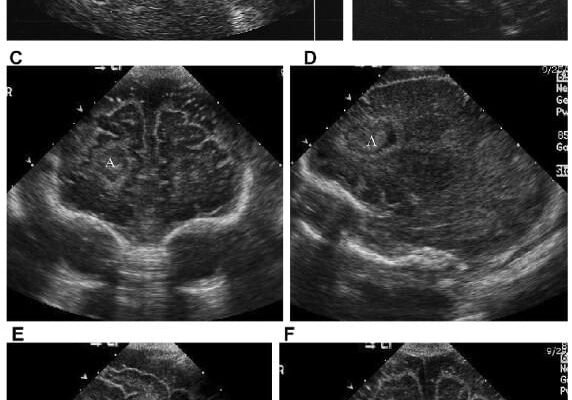

Отже, як його розпізнати? Лікарі можуть використовувати нейросонографію — ультразвукове дослідження мозку малюка. Звучить складно, але це всього лише детальна “фотка” внутрішніх процесів. Окрім того, набряк може проявлятися через зміни у поведінці дитини: напрочуд тихий чи, навпаки, занадто збуджений малюк.